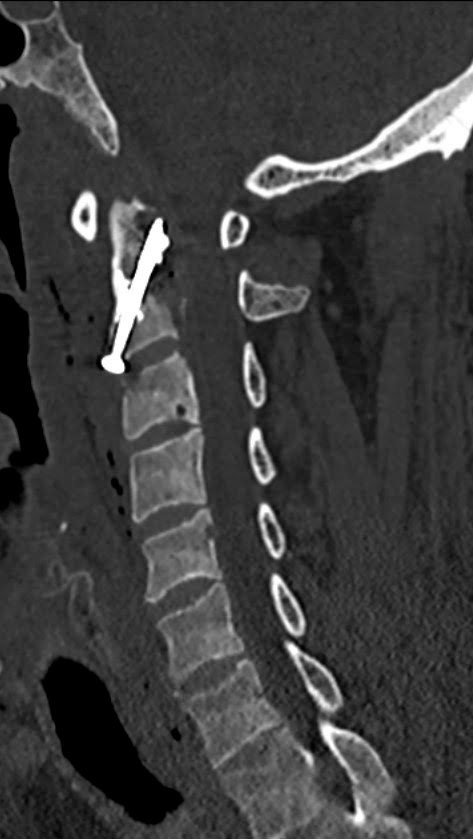

Etter diskusjon med nevrokirurg fant man indikasjon for lokal fiksering med sement og skrue i axis (C2) i narkose (dag 135) og samtidig diagnostisk benbiopsi (figur 2).

Tidspunkt for fiksering ved en eventuell infeksjon er omdiskutert, men man vurderte det som nødvendig med fiksering av dens axis, da den ble ansett for å være ustabil. Det ble av den grunn vurdert at inngrepet ikke kunne utsettes i påvente av annen diagnostikk.

CT av cervikalcolumna etter operasjon viste at skruen og sementen var godt plassert. Det var imidlertid økende osteolytiske forandringer i atlas (C1). Pasienten hadde mindre smerter etter operasjonen og ble skrevet ut i påvente av svar på benbiopsi. Det ble planlagt kontroll-CT av cervikalcolumna etter seks uker.

Smertene som initialt hadde avtatt, økte på ny i styrke. Ny CT av cervikalcolumna tatt poliklinisk seks uker etter operasjon (dag 176) viste progresjon av osteolytiske forandringer med total destruksjon av C3, partiell destruksjon av C4 og betydelig akseavvik i cervikalcolumna og cervikale del av medulla spinalis. Pasienten hadde nå symptomer i form av utstrålende smerter i alle ekstremiteter ved ekstensjon av nakken, og han hadde problemer med å gå. Han ble lagt inn på nevrokirurgisk avdeling (dag 177) og gjennomgikk operasjon i narkose med korpektomi av C3–C5, fremre fiksering med plate og bakre fiksering fra occiput til C6 (dag 180). Det ble tatt ny benbiopsi peroperativt fra corpus av C3–C4.